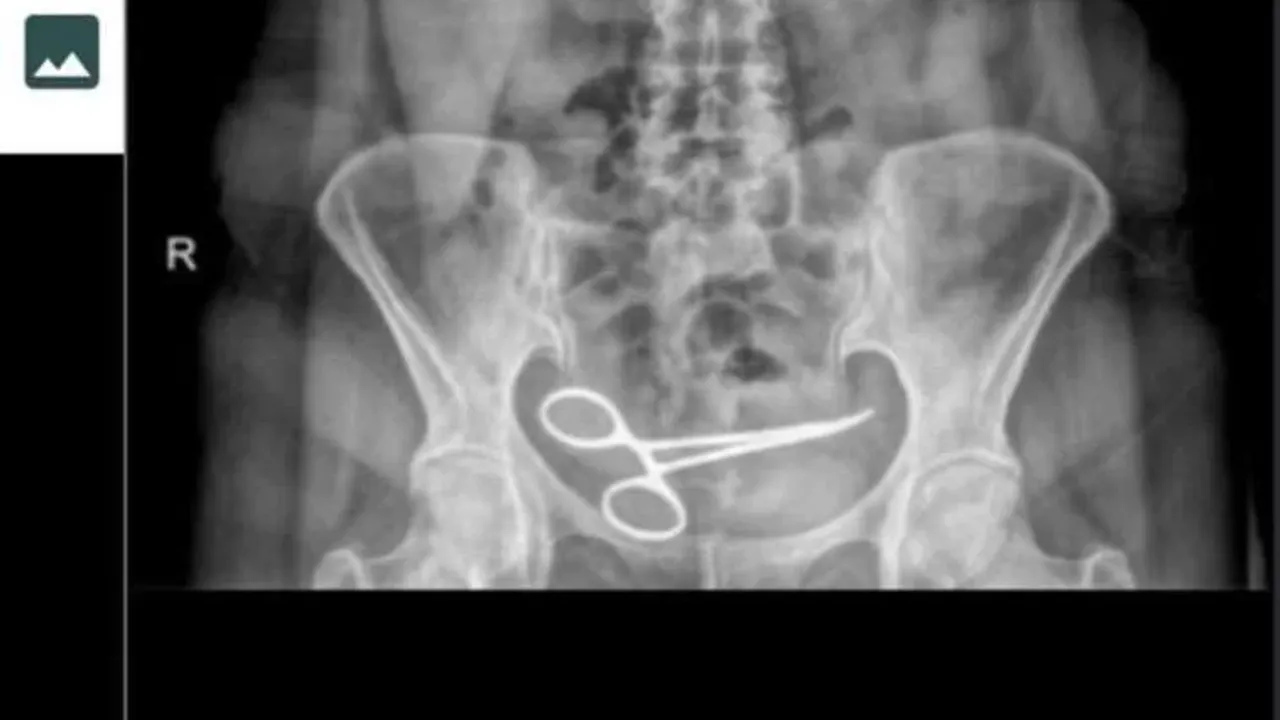

Ankara'da Şadiye Boyun, 28 Aralık 2021 tarihinde Pursaklar ilçesinde, özel hastanede bir kadın hastalığı nedeni ile ameliyat oldu. Ameliyattan 8 ay sonra karın ağrısı şikayeti görülen Boyun, ambulans ile Pursaklar Devlet Hastanesi'ne kaldırıldı. Burada çekilen röntgende Boyun'un ince bağırsağına takılı 12 santim boyunda makas olduğu görüldü. Ardından iddiaya göre, ameliyatın gerçekleştirdiği özel hastaneye haber verildi. Özel hastaneden görevliler geldi.

Görevliler tarafından tekrar özel hastaneye götürülen Boyun’un röntgeni çekildi. Bunun üzerine oğlu Fatih Boyun, durumdan şüphelenerek e-Nabız uygulamasından röntgen sonuçlarına baktı ve annesini Gülhane Eğitim ve Araştırma Hastanesi'ne sevk ettirdi. Şadiye Boyun'un karnındaki makas ameliyatla alındı. Boyun, avukatı aracığıyla, ameliyatı gerçekleştiren doktor ve hastane hakkında suç duyurusunda bulundu.